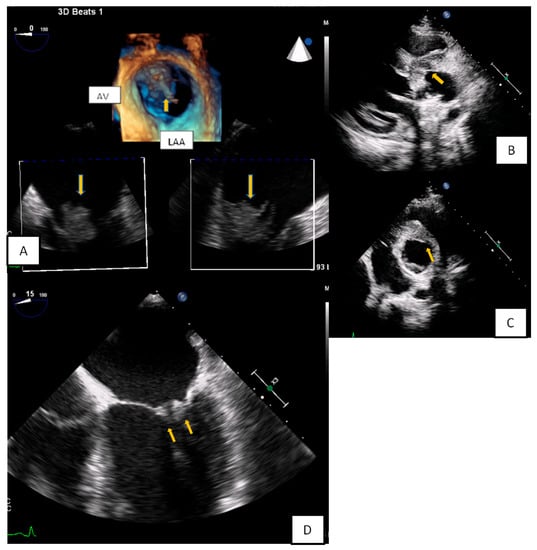

3.1. Transthoracic Echocardiography

3.2. Transesophageal Echocardiography

- Zaragosa-Macias, E.; Chen, M.A.; Gill, E.A. Real time three-dimensional echocardiography evaluation of intracardiac masses. Echocardiography 2012, 29, 207–219. [Google Scholar] [CrossRef] [PubMed]

- Aggeli, C.; Poulidakis, E.; Felekos, I.; Aggeli, A.; Stefanadis, C. An octopus-like myxoma depicted by real-time 3D transesophageal echocardiography. Hell. J. Cardiol. 2012, 53, 470–471. [Google Scholar]